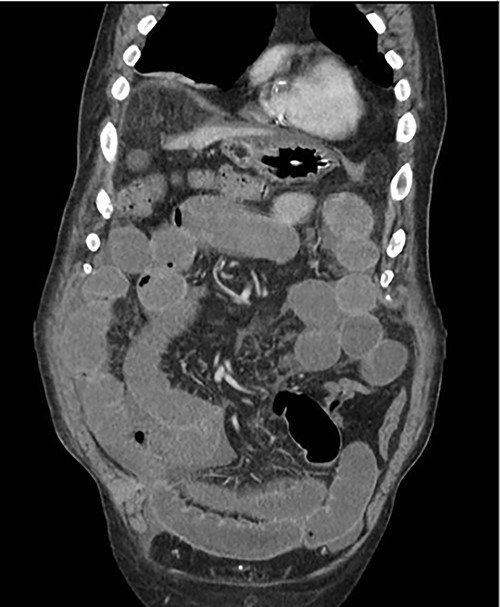

An 81-year-old male with past medical history of coronary artery disease, peripheral arterial disease, hypertension, dyslipidemia, hypothyroidism, benign prostatic hyperplasia, osteoarthritis, sleep apnea, gout and 10-pack year smoking history presented with complaints of abdominal distention and bloating. Patient had been suffering from recurrent bouts of constipation for ~2 weeks with last bowel movement noted to be over 2 days prior to presentation. Patient also complained of numerous episodes of nonbilious non-bloody vomiting. Abdominal computed tomography (CT) scan (Fig. 1) presented findings of a small bowel obstruction with transition point at the level of the terminal ileum. Notably, patient was also positive for coronavirus disease 2019 (COVID-19) infection. General surgery was consulted, and patient was initially treated with non-operative management with nasogastric tube and serial abdominal exams. However, a repeat abdominal CT scan (Fig. 2) after 6 days of attempted conservative management showed persistent diffuse small bowel distention and increased ascites. This combined with the fact that the patient had no prior colonoscopies or abdominal surgeries prompted surgical exploration. Patient underwent exploratory laparotomy; intraoperatively, he was found to have a palpable mass at the terminal ileum. A right hemicolectomy with a side-to-side functional end-to-end ileocolonic primary anastomosis was performed. Final pathology revealed diffuse peritoneal malignant mesothelioma with no nodal involvement and negative margins.

Mesothelioma is a rare and lethal neoplasm of serosal membranes, most commonly affecting the pleura, and less commonly the peritoneum, pericardium and tunica vaginalis. Malignant peritoneal mesothelioma is a more aggressive variant of this disease, accounting for ~10% of cases of mesothelioma. Rates of peritoneal mesothelioma are dependent on geographic locations. In industrialized areas, incidence rates range from 0.2 to 3 cases per million, given their increased exposure to asbestos which is the known main cause of peritoneal mesothelioma. Other linked exposure risks include, exposure to erionite, thorotrast, mica and radiation [1, 2]. Our patient had a history of working in a factory that manufactured wire hangers. This could have been a potential source of asbestos exposure. Patient presentation is often vague, symptoms include abdominal pain, ascites, shortness of breath, weight loss, anorexia, diarrhea and vomiting. Abdominal CT scan is often relied on to assist with localization of a mass for fluid sampling as Peritoneal malignant mesothelioma is typically diagnosed through fluid cytology [3]. The World Health Organization (WHO) classifies malignant peritoneal mesothelioma into three histologic subtypes: epithelioid, sarcomatoid and biphasic/mixed [2]. Pathologic evaluation of our patients’ specimen displayed tubulopapillary architecture with monomorphic epithelioid cytomorphology. Tumor noted to penetrate through the ileocecal muscularis propria and submucosa. In addition, immunohistochemical analysis showed strong positive reactions with Calretinin, CK5, CK6, WT-1 and D2–40. These findings supported a diagnosis of diffuse peritoneal malignant mesothelioma, epithelioid subtype which is the most common [2]. Treatment of malignant peritoneal mesothelioma involves neoadjuvant cytoreductive surgery in combination with hyperthermic intraperitoneal chemotherapy with cisplatin and doxorubicin. These perioperative treatments are followed by adjuvant intraperitoneal paclitaxel and second-look cytoreduction [4, 5]. Prognosis of peritoneal mesothelioma is dictated by many factors including completeness of cytoreduction and patient gender. Prognosis is improved in female gender, those who receive intraperitoneal chemotherapy, and in patients who receive cytoreduction. Using a multimodal treatment approach has been reported to result in a median survival of 4–5 years [6]. Given our patient’s atypical presentation with severe small bowel obstruction he was taken for emergent surgical resection. This case points to the fact that malignant peritoneal mesothelioma may be a differential diagnosis in a patient with a small bowel obstruction. Timely and accurate diagnosis and staging can allow for proper treatment protocols and increased longevity after curative surgery. Our patient is currently receiving immunotherapy with nivolumab and ipilimumab due to refusal of chemotherapy treatment. Currently, there has been no evidence of distant metastatic disease after repeat CT and positron emission tomography scans; however, he was found to have mass in the right lateral anterior abdominal wall and peritoneum.